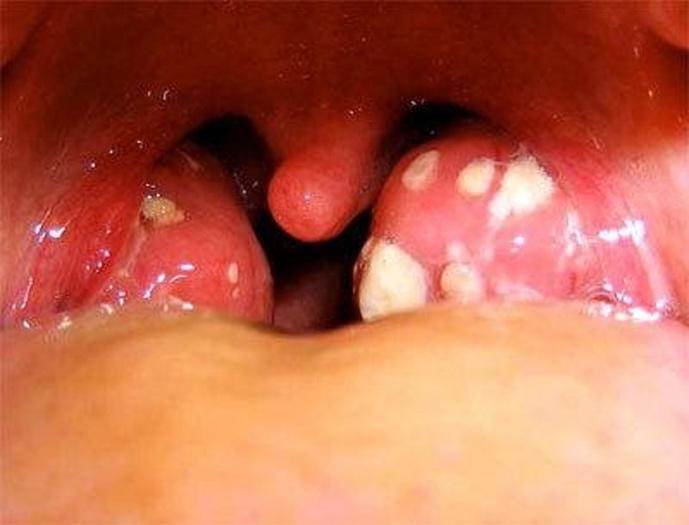

На начальных этапах заболевания миндалины становятся увеличенными, отечными и с ярким блеском. На их поверхности появляются мелкие беловато-желтые образования — это нагноившиеся фолликулы.

Диагноз основывается на симптоматике, анамнезе и жалобах пациента. Существенным этапом является фарингоскопия. При осмотре часто наблюдаются покраснение и отек миндалин, наличие гнойных пробок и фолликулов, что является характерным признаком данного заболевания.